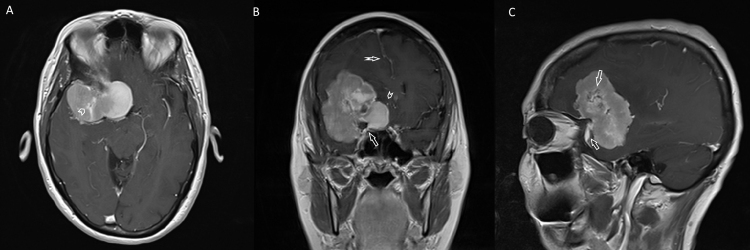

Fig. 1.

Axial computed tomography image without contrast, illustrating right sided sphenoid wing meningioma (notched arrow) measuring 5.4 cm × 4 cm × 5.3 cm (transverse × anterior-posterior × cranial – caudal). The bone along the right sphenoid wing, the anterior and posterior clinoid processes is hyperostotic (arrow). There was 1 cm of midline shift and vasogenic edema present in the right frontal and temporal lobes (not shown). The findings were consistent with meningioma and this was compared to the CT head from 10 years prior which had no evidence of lesion.

Fig. 2.

From left to right – (A) axial, (B) coronal and (C) sagittal magnetic resonance images (MRI) with gadolinium of right sided sphenoid wing meningioma in index case. A characteristic dural tail is present shown in C by the notched arrow. The lesion extends along the planum sphenoidale. There is no intraorbital extension of the lesion. In (A) the chevron illustrates a vessel flow void traveling through the lesion. In (B) the arrow shows area of internal carotid artery encasement, the chevron illustrates the anterior cerebral artery flow voids displaced medially by the lesion and the notched arrow shows the midline shift of the falx cerebri. In (C) the arrow again illustrates vessel flow voids traveling through the lesion.